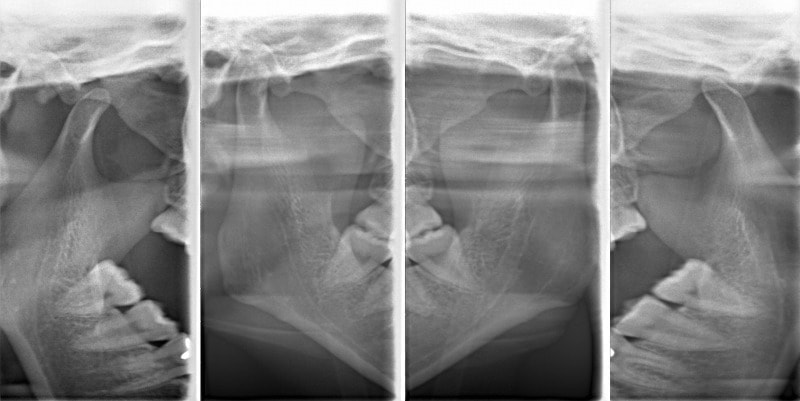

検査時顎関節レントゲン

関節頭に変形が認められます。